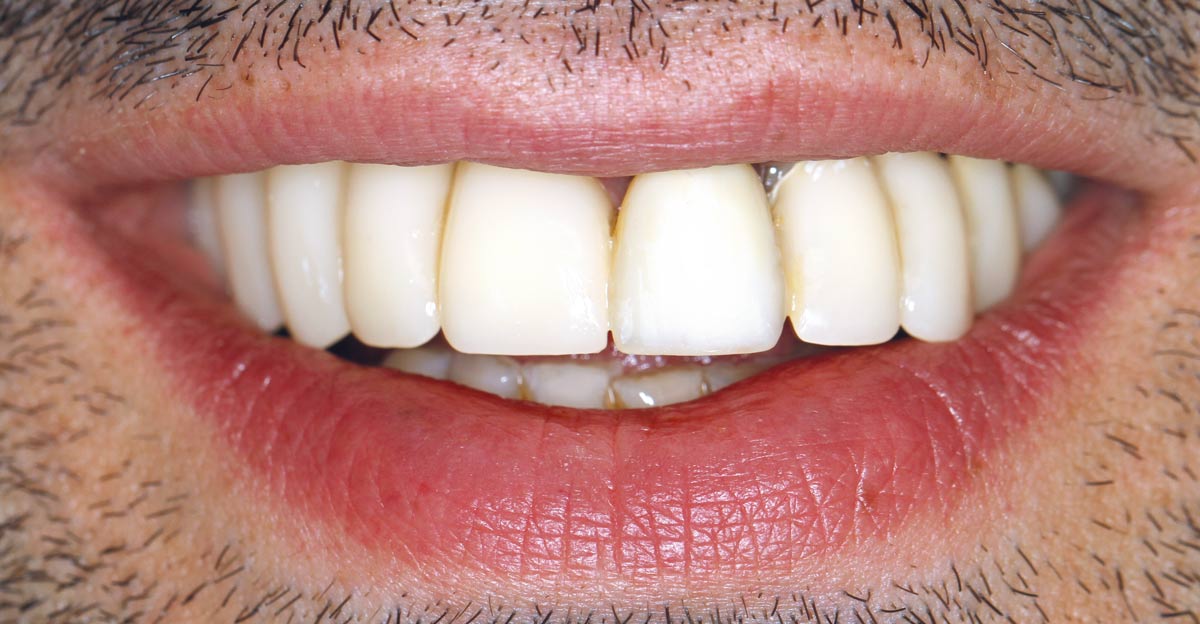

Restoration of all four incisors with two maxgraft® bonering - Dr. B Giesenhagen

Initial situation pre-op: Central incisors with mobility 3